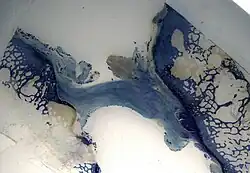

Die dynamisch intraligamentäre Stabilisation wurde zuerst am Tiermodell (Schafe) getestet. Die Resultate konnten belegen, dass ein Kreuzband durchaus ein Heilungspotential besitzt.[1]

Insbesondere zeigten die histologischen Studien ein schnelles Einwachsen von Blutgefäßen in den gerissenen Anteil des Bandes sowie erhaltene Tiefenrezeptoren. Im biomechanischen Test konnte eine zunehmende mechanische Stabilität des Bandes gemessen werden, was als beweisend gilt für die biologische Heilung eines Bandes.